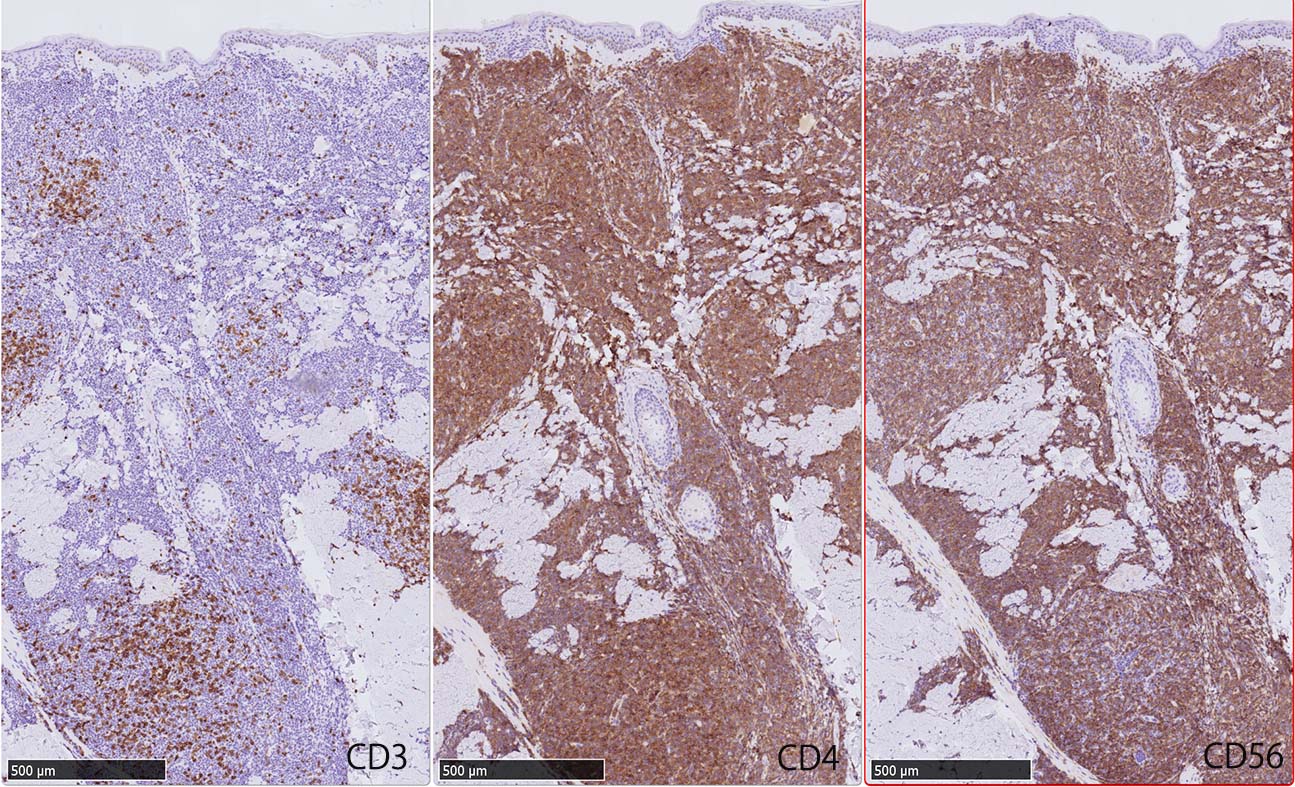

免疫染色

IWT-case: 4つの点で囲んだ紅斑から生検.

腫瘍細胞は真皮を主座として, 皮下脂肪織まで, びまん性かつ単調monotonousに増殖することが多く, 表皮向性はみられない. 本例では血管や付属器中心あるいは脂肪織内に結節状の浸潤増殖を示した.

本例皮膚真皮増殖細胞はCD4+, CD56+, CD123+, CD303+, lysozyme(-). がん研有明病院, Sakamoto K, Takeuchi K先生にconsultationを行い, TCF4, TCL1の陽性が確認された.(consultationを受けていただいた両先生に深謝いたします.)

CD4は染まりすぎの感がある(濃く染まる細胞はCD4+ T-cellかもしれない). CD56, CD123が陽性で可能性が高くなり, BPDCNの診断にはCD34は陰性であることが必要

TCF4、CD123、TCL1をconsultationにより染色していただき, 陽性を確認した. CD34-, lysozyme-, CD123(おいてある病院は少ないかも)をしらべて, BPDCN研究会あてconsultationをする流れでしょうか.